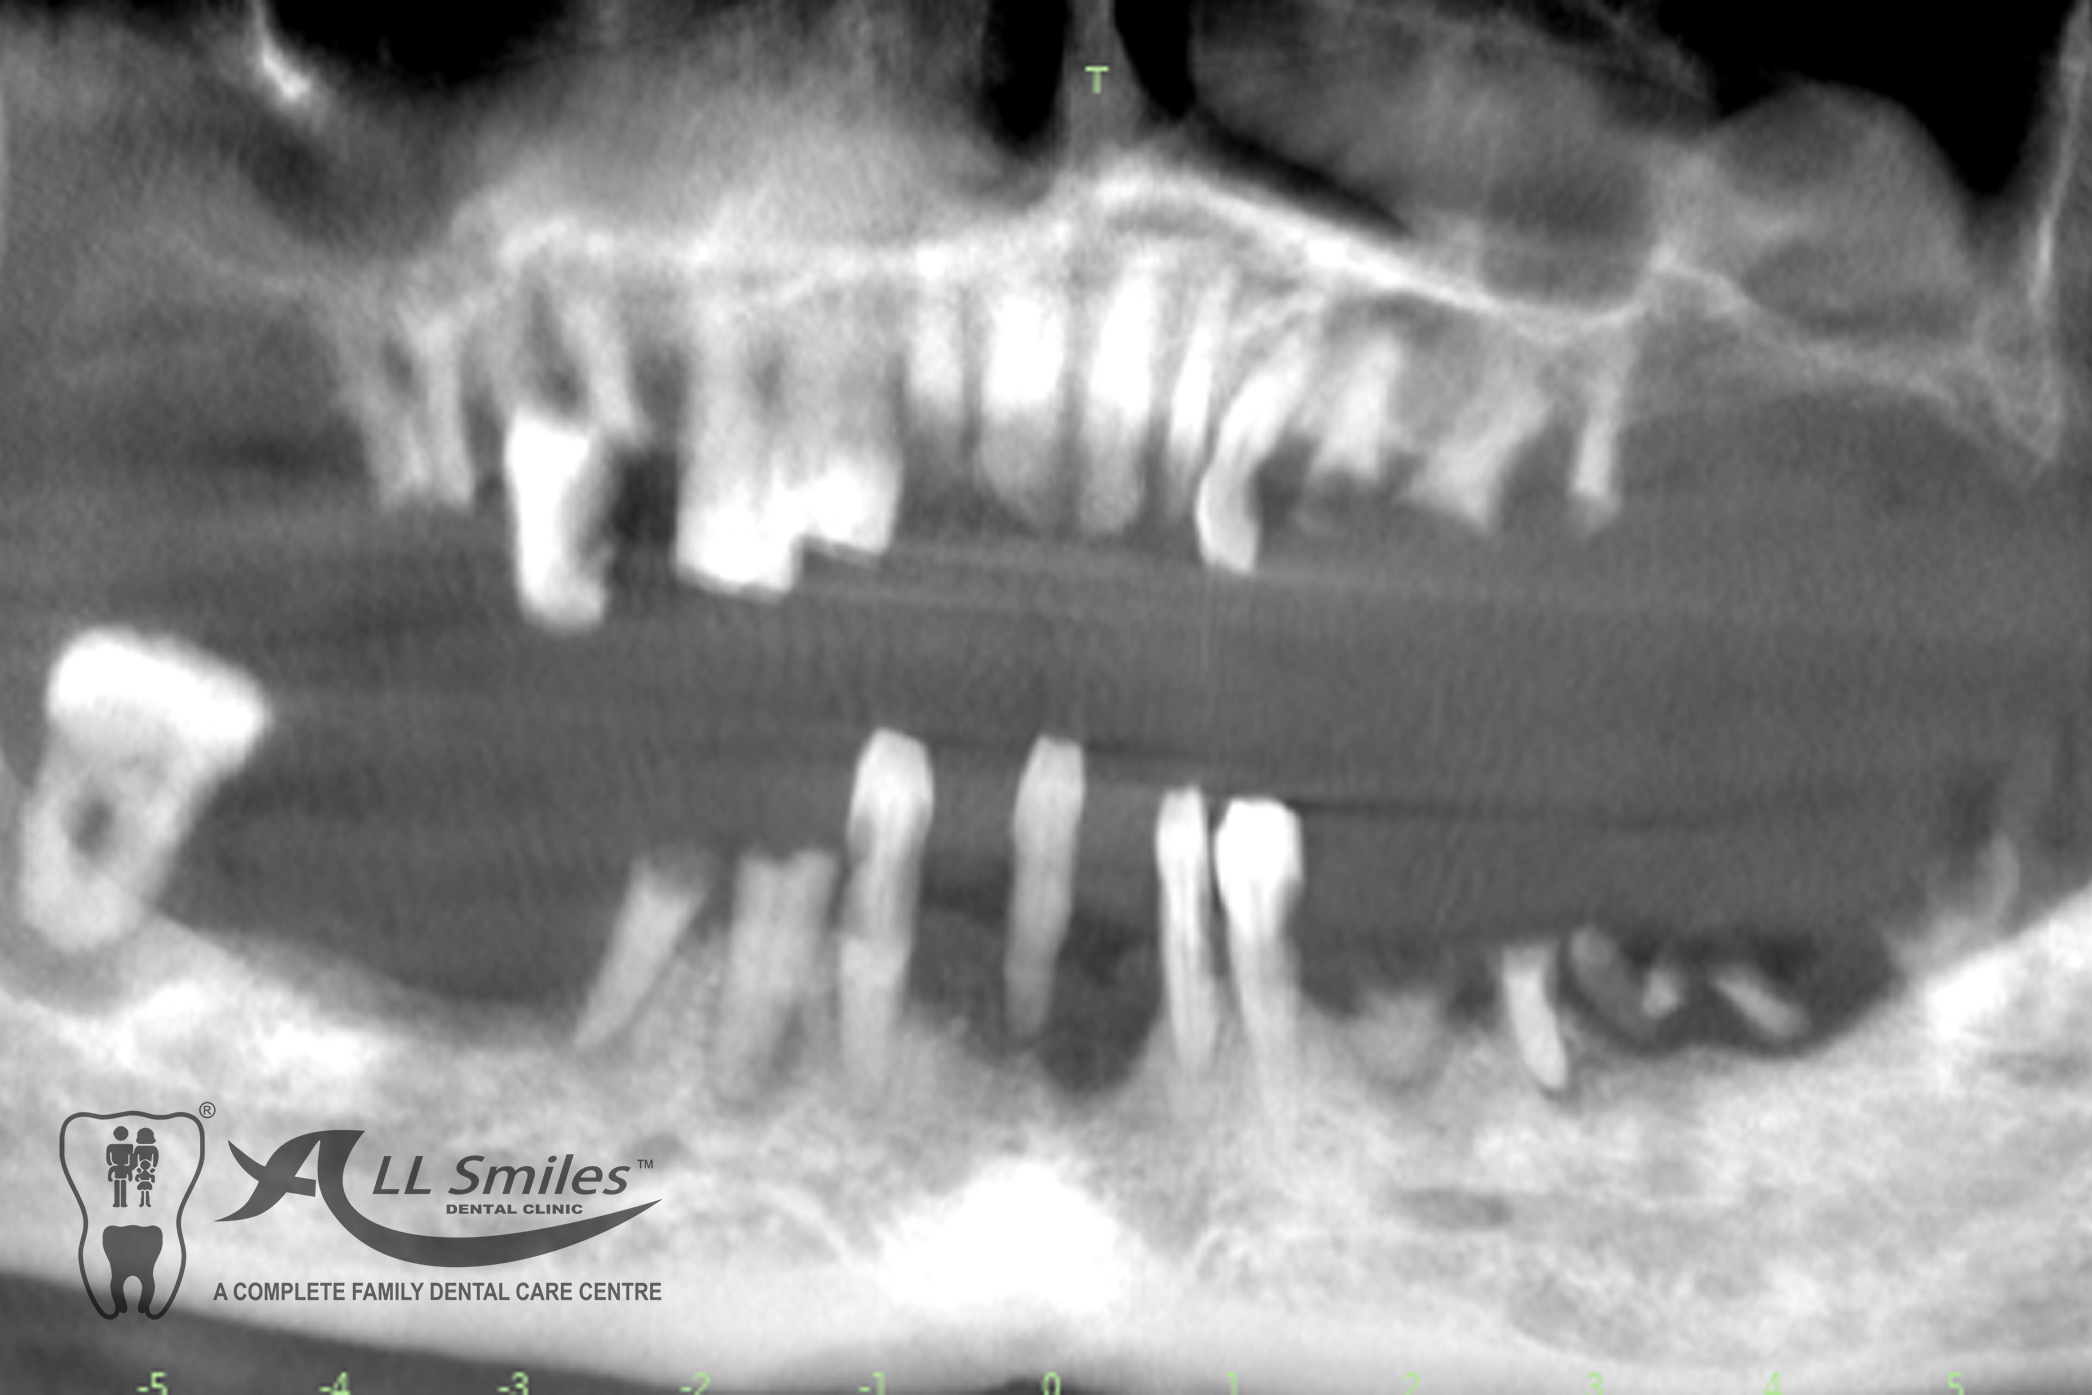

Successful tooth implant procedures require a foundation of healthy bone and gums. Before starting an implant procedure, we’ll assess your health and work with you to create a plan to resolve gum disease or other issues. Expect your first visit to take about 90 minutes and include an exam, x-rays, thorough cleaning, and plenty of time to speak with your dentist.

The dental implant procedure is divided into stages. The first stage involves the placement of the implant into the jawbone, which usually takes 1-2 hours. After this, there is a healing period of 6-8 weeks during which the implant fuses with the surrounding bone tissue. Once the implant has healed, a small connector called an abutment is attached to the implant, followed by the attachment of a dental crown, bridge, or denture.